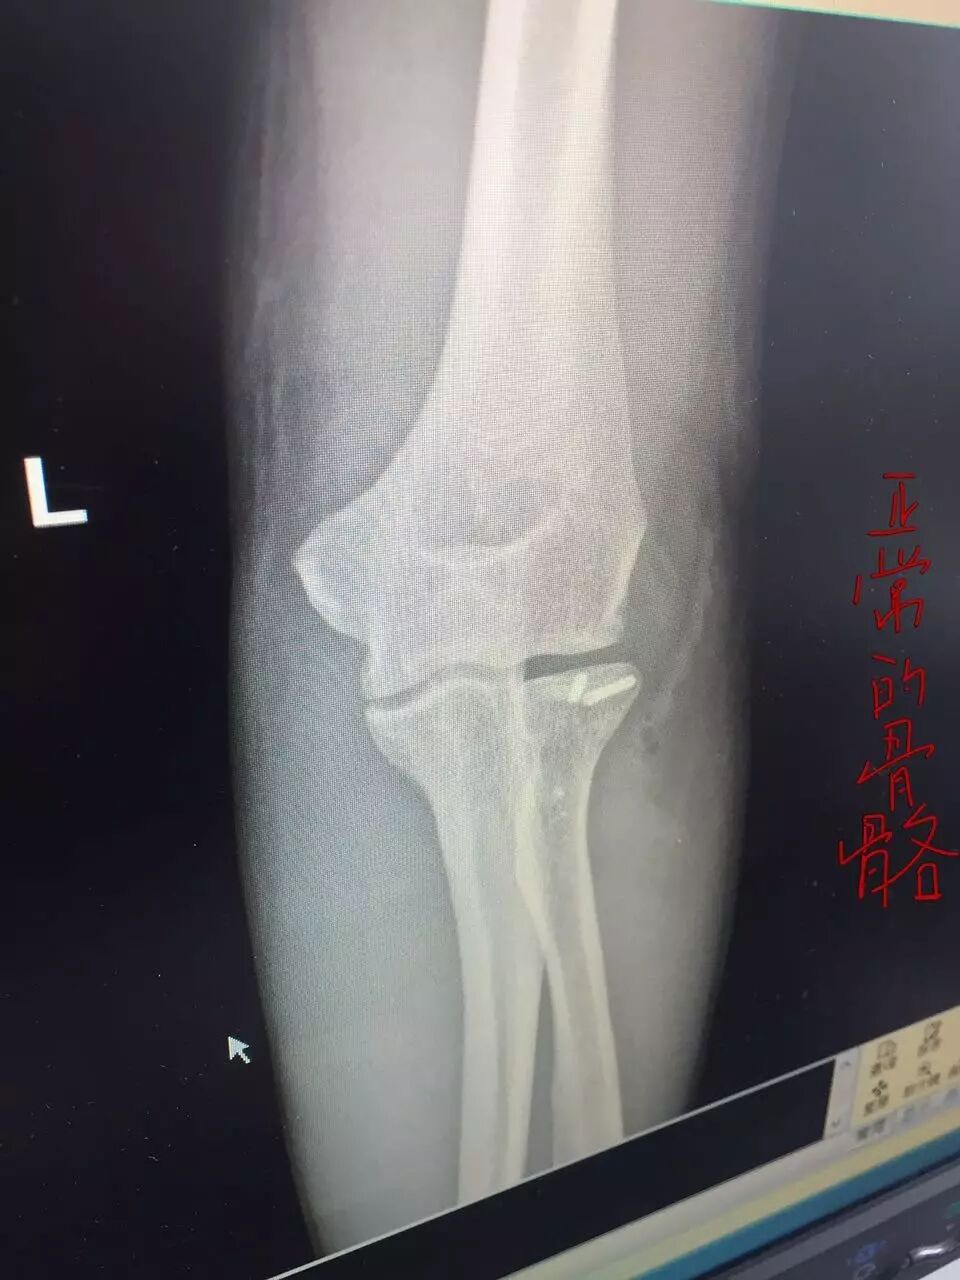

老鄉(xiāng)給記者看,上午醫(yī)生給的檢查結(jié)果,說(shuō)這兩天還要做很多檢查,還要?jiǎng)邮中g(shù)。

老人受傷圖

↓↓↓↓↓↓

(前方高能… 謹(jǐn)慎…)

記者在急診科的檢查結(jié)果上看到,初步診斷老人面部損傷、下肢損傷、骼骨骨折、肱骨骨折、上肢皮膚裂傷。于是記者找到管床的醫(yī)生,他告訴記者,最嚴(yán)重的是左手,里面的骨頭已經(jīng)碎了,等其他傷口消炎后一周左右要做“骨骼切開復(fù)位內(nèi)固定”手術(shù),拼接骨頭,安裝鋼板,要休養(yǎng)三個(gè)月到半年才能工作。醫(yī)生說(shuō),擔(dān)心病人頭部有受傷,還要做腦部CT平掃。